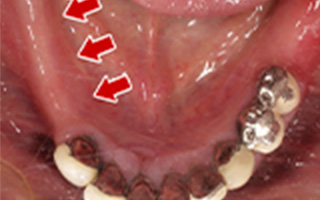

Before

After

| 60歳 男性 | 歯科大学病院 教授からの紹介 ご本人は産婦人科医 |

|---|---|

| 主訴 | 左下に歯が無くて食事がしずらい |

| 処置内容 | 2本インプラント埋入+再生処置 |

| 治療費用 | 下顎: 約80万円(税込) |

| 治療期間 | 下顎: 6ヶ月 |

| リスク | 術後の腫れ、痛み(ピークは3日後、1週間で軽減) |